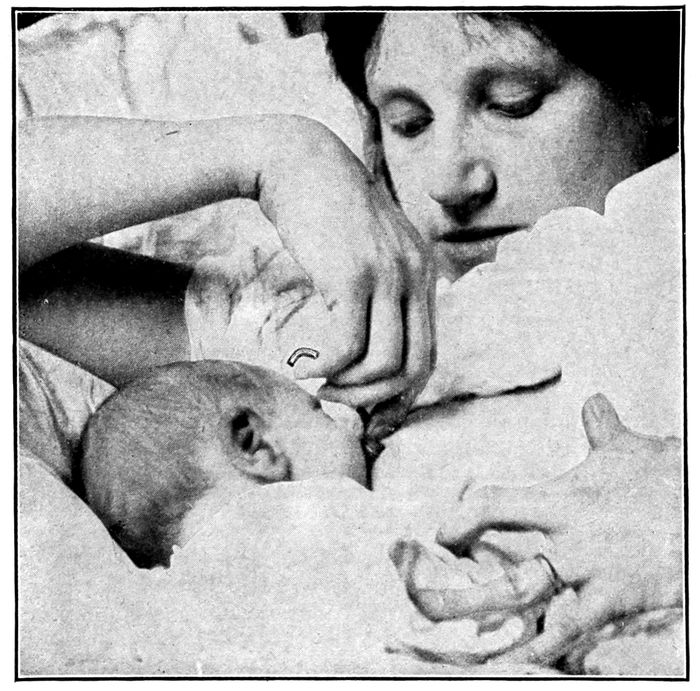

Proper position of mother while nursing child |

274 |